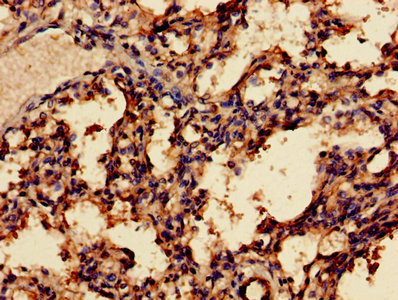

Immunohistochemistry of paraffin-embedded human breast cancer using CSB-PA013334LA01HU at dilution of 1:100